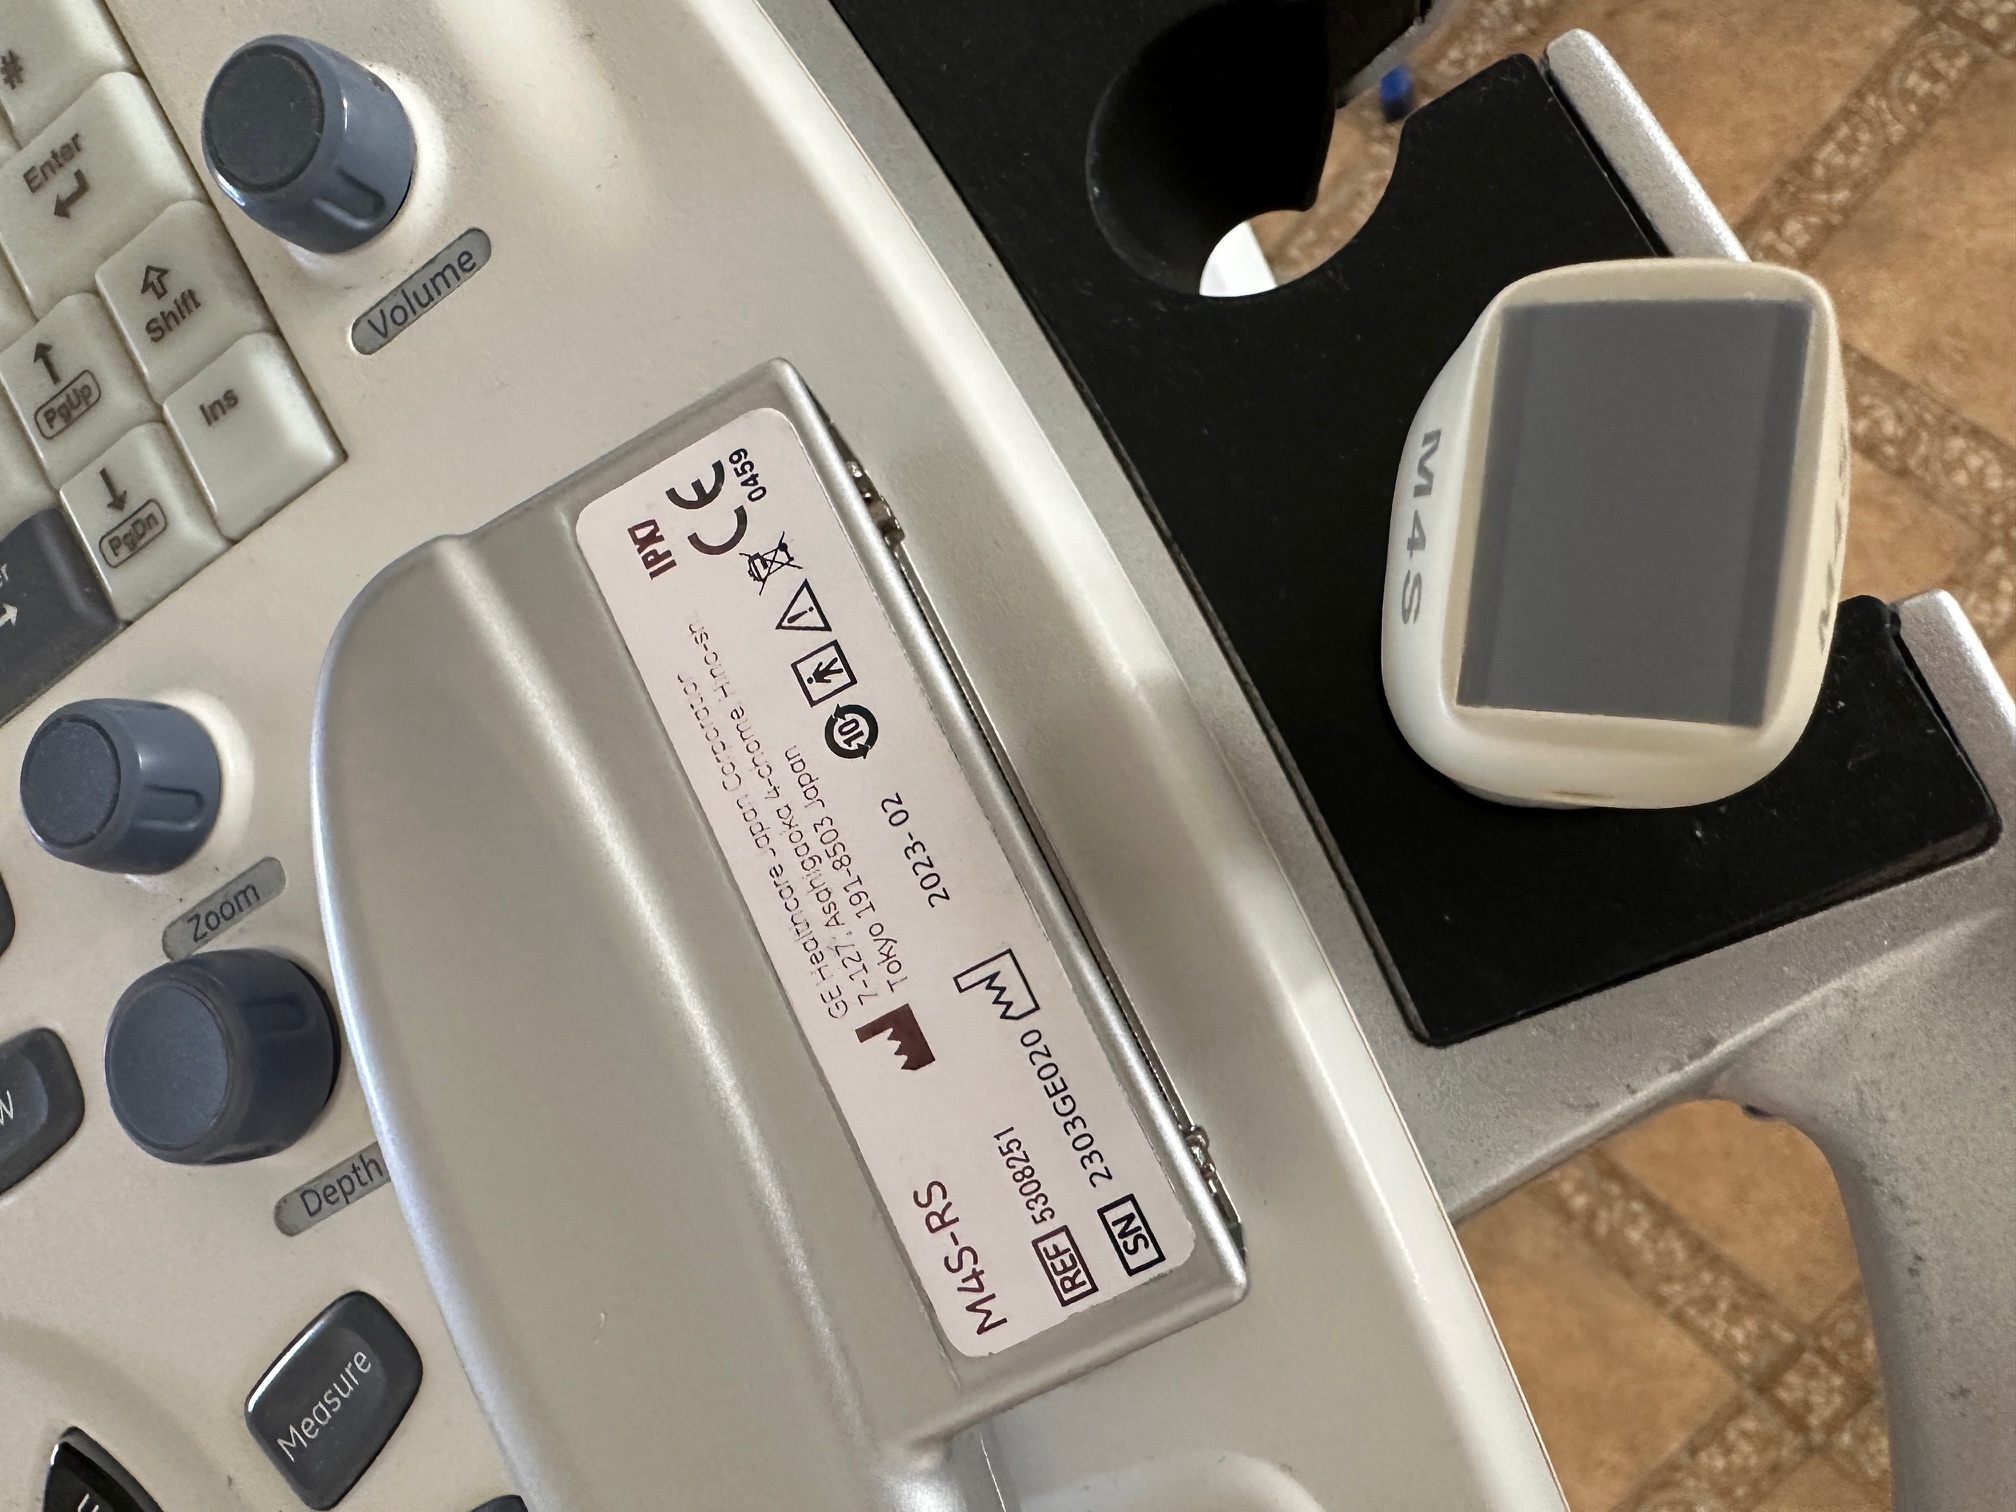

oferuję echokardiograf Vivid S6 z 2014r z głowicą M4S Rs z 2023r.

Głowica praktycznie bez śladów użytkowania - wykonane maksymalnie 100 badań.

oferuję echokardiograf Vivid S6 z 2014r z głowicą M4S Rs z 2023r.

Głowica praktycznie bez śladów użytkowania - wykonane maksymalnie 100 badań.